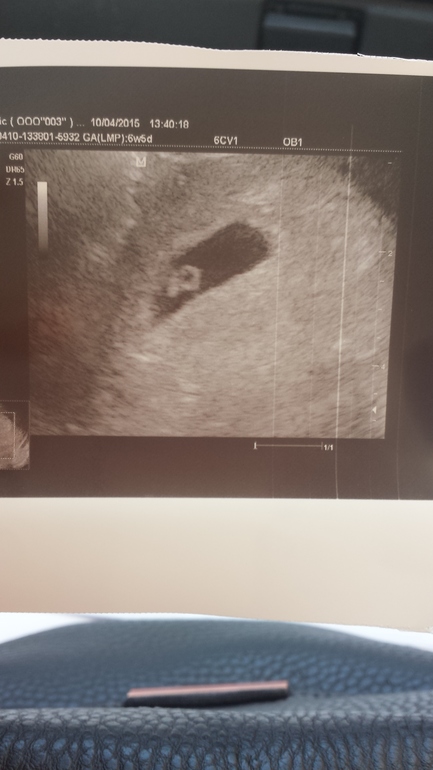

Сходили на УЗИ!

УЗИ, КТГ, доплерНаш малыш в матке! Эмбриончик 5,6мм, сердцебиение есть! я его видела, это так трогательно! Эндометрий хороший, отслоек ттт нет, все хорошо! Только вот ШМ 35*24, не маловата? И эмбриональный срок 4-5 недель, О на 19ДЦ была, врач сказала все нормально. А вот наше чудо!

и заключение УЗИ